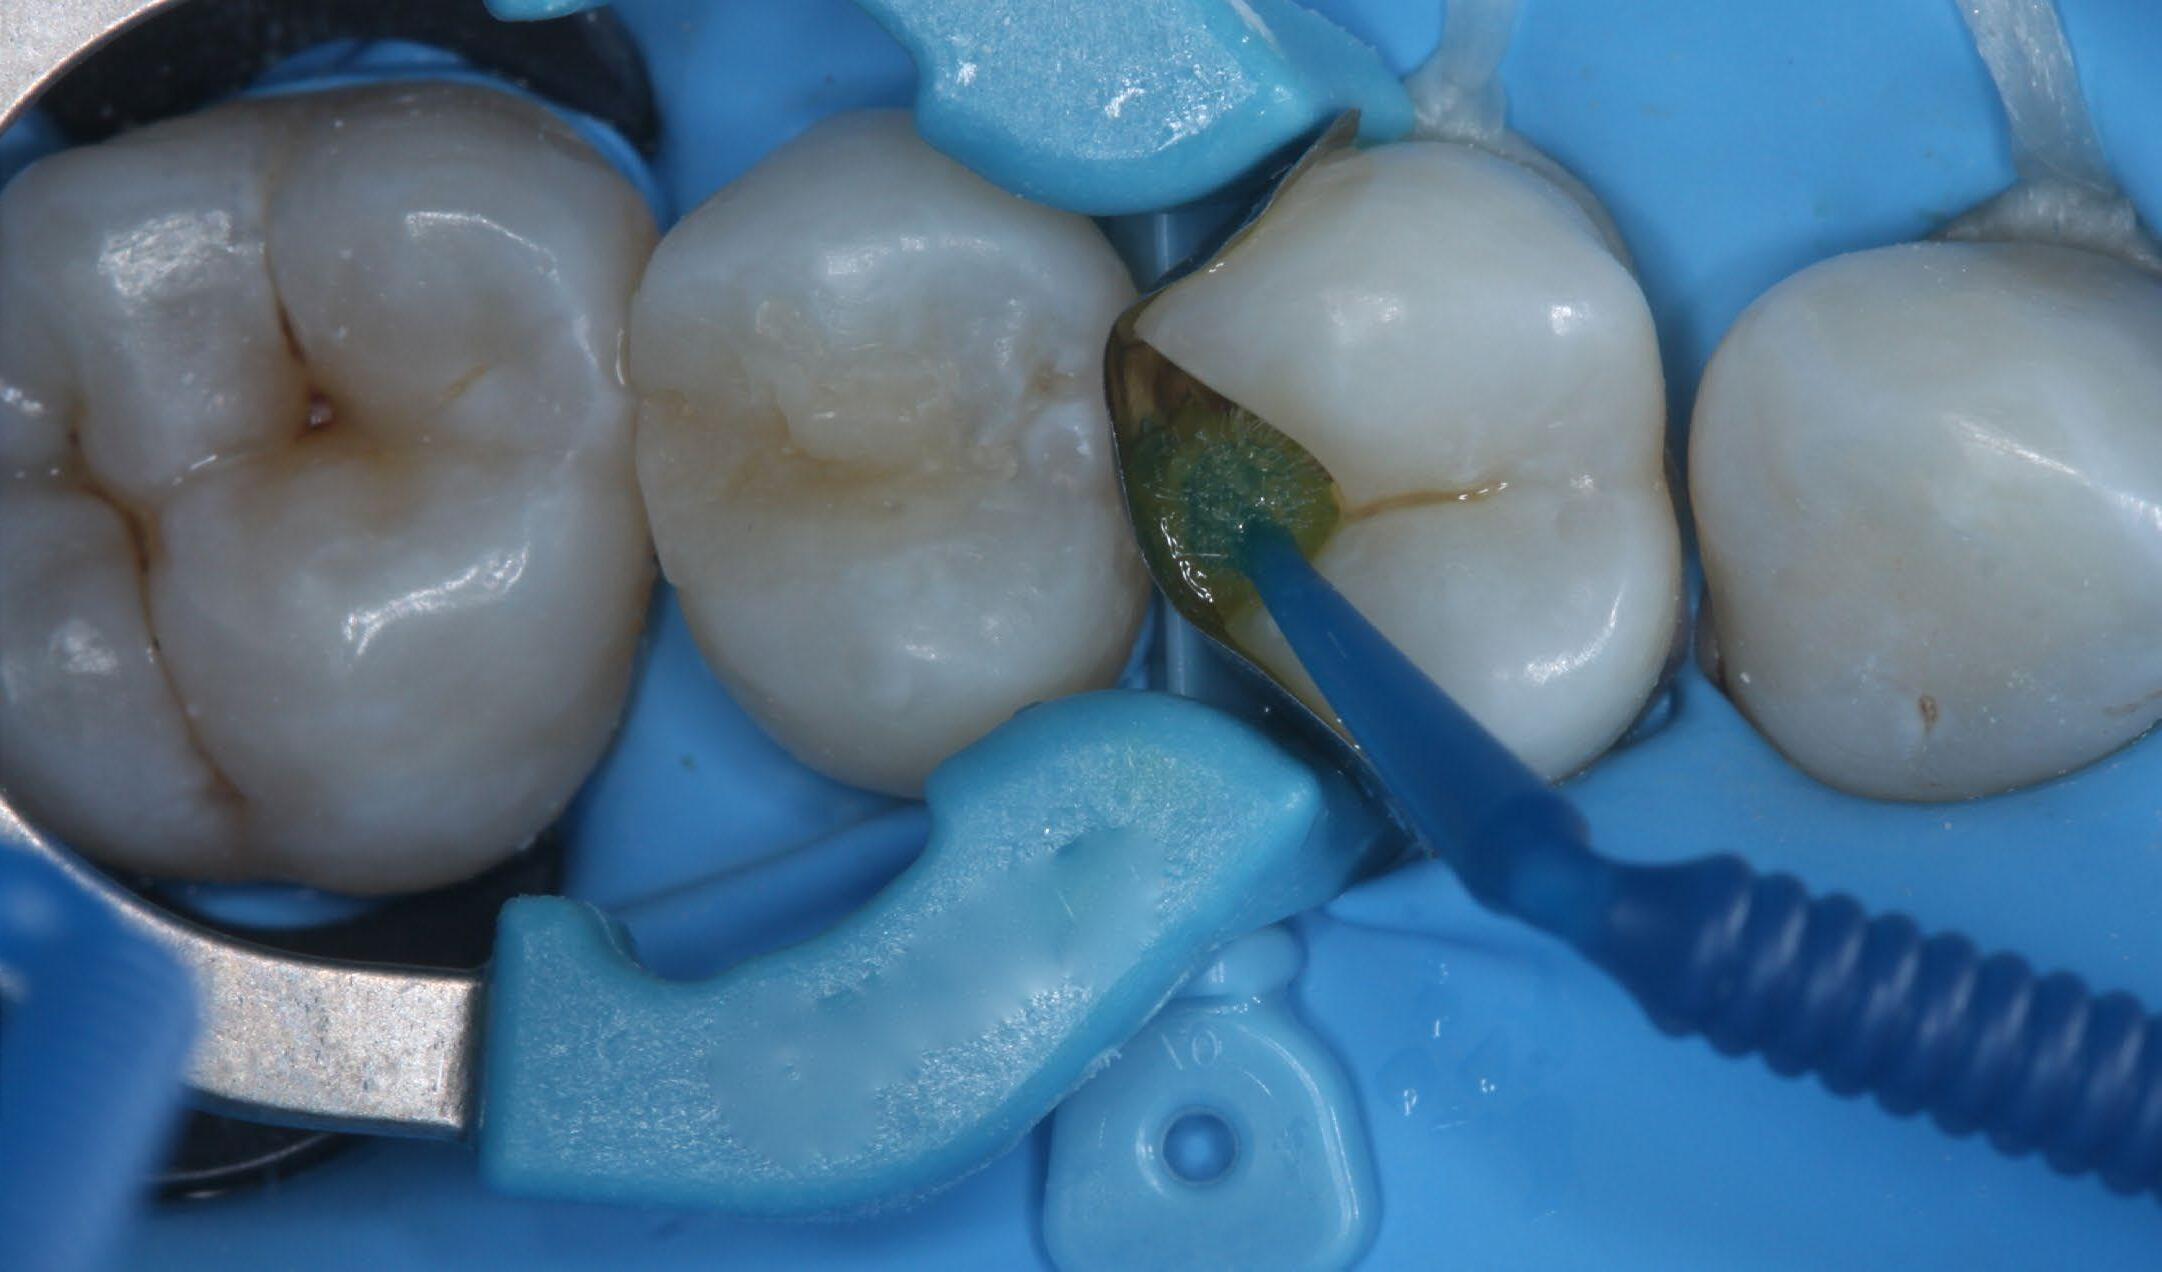

Fig. 5: Selective enamel etch. Phosphoric acid gel was applied for 15 seconds, rinsed and lightly dried. Fig. 6: Adhesive was applied on dentin, rubbed in for 20 seconds, air dried for 5 seconds and light cured for 10 seconds.* Hidden Proximal Caries | Posterior continues next page >>> Fig. 7: After adaptation of the matrix system, the first layer of 3M™ Filtek™ Universal Restorative, shade A2, was placed. Fig. 8: Placement of the restoration is completed.